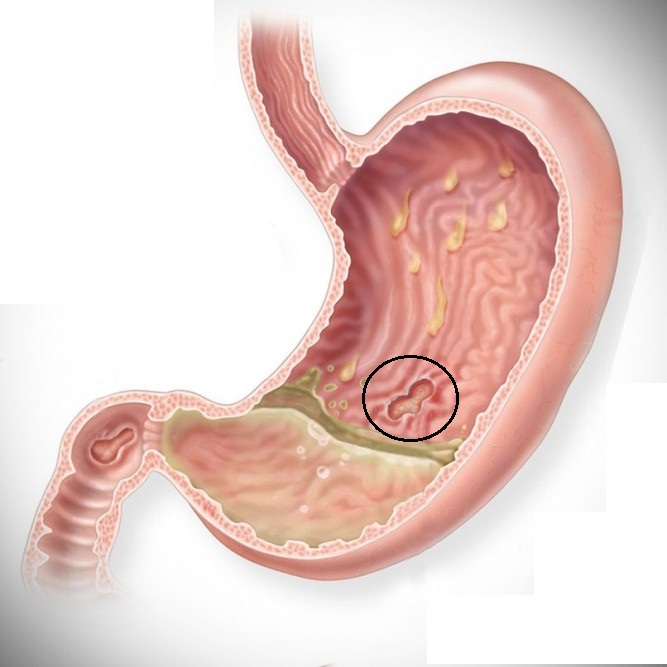

Dvanáctník (= dvanácterník) - je to počáteční nejkratší část tenkého střeva, do které ústí žaludek a vývody slinivky břišní a žlučníku. Latinský název je duodenum, který vychází z označení přibližné délky dvanácterníku 12 palců. Je to místo častého výskytu peptického vředu neboli defektu sliznice dvanácterníku, což souvisí s infekcí bakterií Helicobacterpylori. Vředy jsou civilizační onemocnění, které postihuje spíše muže mezi 30. až 40. rokem než ženy.

Dvanáctník (= dvanácterník) - je to počáteční nejkratší část tenkého střeva, do které ústí žaludek a vývody slinivky břišní a žlučníku. Latinský název je duodenum, který vychází z označení přibližné délky dvanácterníku 12 palců. Je to místo častého výskytu peptického vředu neboli defektu sliznice dvanácterníku, což souvisí s infekcí bakterií Helicobacterpylori. Vředy jsou civilizační onemocnění, které postihuje spíše muže mezi 30. až 40. rokem než ženy.

Přispívá k tomu nervové vypětí, kouření, požívání alkoholu a špatná strava, která vyvolává produkci nadbytku žaludečních šťáv.